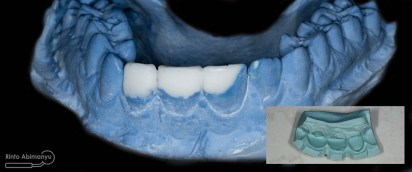

Semua akses pada saat perawatan saluran akar ditutup dengan resin komposit, setelah itu gigi pasien dicetak untuk keperluan pembuatan wax up… Setelah dicetak pasien pulang…

Wax up ini merupakan proses yang penting bila kita berhadapan dengan kasus yang kondisi giginya tidak utuh, dari sanalah nanti kita mendapatkan visualisasi perkiraan hasil akhir perawatan… Wax up bisa dilakukan sendiri bila kita mempunyai alat dan bahan yang diperlukan atau bisa dikirimkan ke lab… Tapi saya mempunyai istri yang juga seorang prostodontis jadi saya minta tolong dia untuk melakukan wax up hehehe :p

Model yang sudah diwax up kemudian saya cetak dengan putty double impression yang nanti cetakan tersebut dijadikan sebagai silicone index pembuatan mahkota sementara…